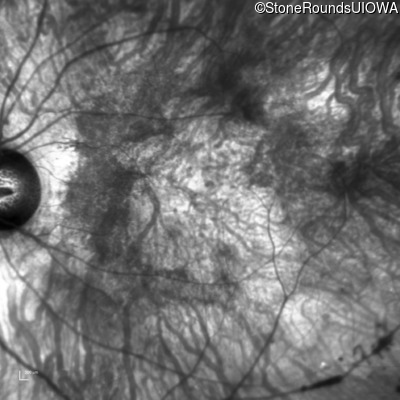

Age at visit: 38 years

This 38 year old woman had normal vision until age 22 when she noticed poor night vision when working as a camp counselor after college. Her hearing loss was first noticed at age 3 and was correctable with hearing aids.

Diagnosis & molecular findings

Usher Syndrome TUBB4B Arg262Gln CGG>CAG   AD